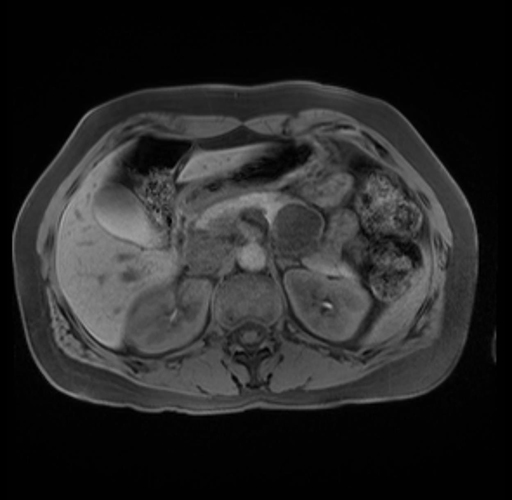

Imaging Analysis

Look through the patient's CT scan to identify any areas of concern for the necessary procedure.

Based on your CT findings, which issue(s) are present and would give reason for "planned slowing down moment(s)" in this case?

Considering a standard distal pancreatectomy procedure, what step(s) of the operation would you do differently in this case?